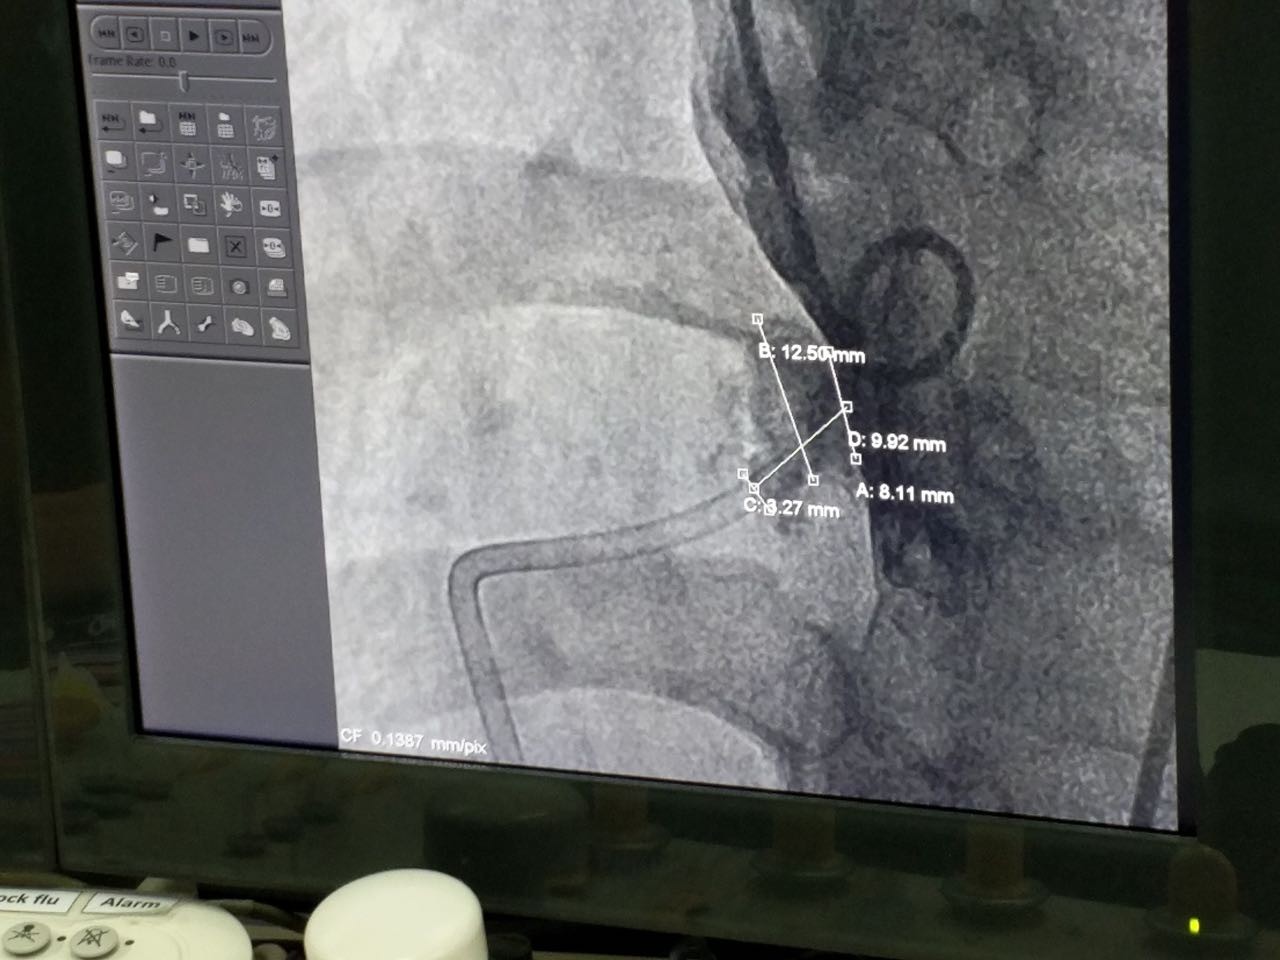

第四例手术患者经诊断为膜周部室距离缺损并伴有室缺瘤。术中丈量患者瘤体直径为12.5mm,左室入口为9.92mm,右室出口为3.27mm,且其室距离缺损地位较为特殊,位于自动脉瓣正后方并非?拷獍。病人同时拥有三尖瓣反流的症状。本例手术的重要术者Dr.Pimpak Prachasilchai选用俄罗斯贵宾会集团科技公司型号为LT-MFO-8-6的KONAR-MF?多职能封堵器,通过自动脉蹊径开释成功。病人缺损部位封堵齐全,无残存分流,三尖瓣未受滋扰。

(术中造影)